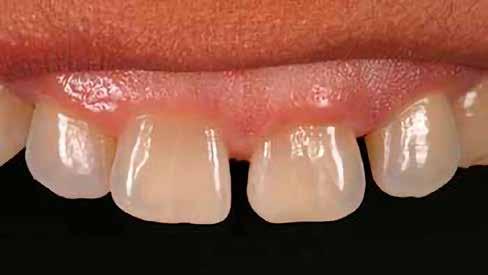

Egy 30 éves, negatív kórtörténettel rendelkező beteg azzal a kéréssel fordult hozzánk, hogy cseréljük ki az UR1 traumája után, 10 évvel korábban készült korábbi kompozit-helyreállítást.

A klinikai vizsgálat során az UR1 reagál a viabilitási tesztre, és az ugyanazon a napon készült röntgenfelvételen nem mutat periapikális elváltozásokat (1. ábra).

Az UR1 elszíneződött, és palatálisabb helyzetben van, mint az ellenoldali központi UL1 (2. ábra)

Az esztétikai elemzés a gingivális zenit aszimmetriáját mutatja az UR1 és az UL1 között. Parodontális szonda segítségével, plexusérzéstelenítés után, az IA

típusú funkcionális hám megváltozott passzív erupcióját igazoljuk Coslet és mtsai. osztályozása szerint (3. ábra)

A lehető legkonzervatívabb helyreállító kezelés elvégzése érdekében a páciensnél, figyelembe véve a megtartott fogelem korát és vitalitását, a tervezés és a diagnosztikai felviaszolás után a közvetlen kompozit-helyreállítás elvégzése mellett döntünk.